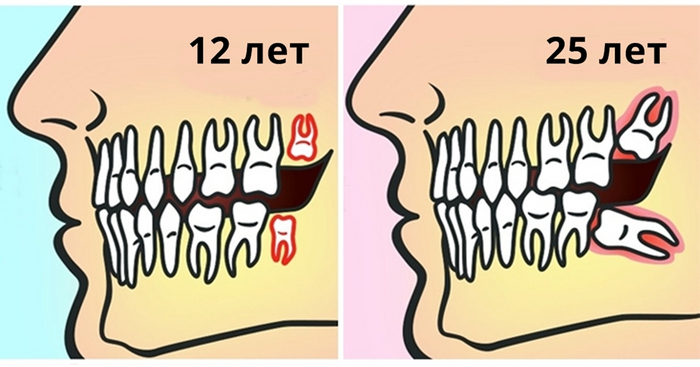

Зубы мудрости бывают разные

Прорезавшиеся, дистопированные, полуретинированные и ретинированные.

Дистопированные зубы- прорезались, но не там, где надо и так, как надо

Полуретинированные- вылезли из кости, а через слизистую не шмогли

Ретинированные- те, которые сидят полностью в кости

Несмотря на отличия в расположении, принцип их удаления примерно одинаков